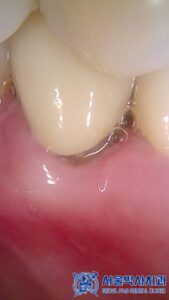

또한 추가적으로

환자분의 앞니 부분에서

치경부 마모가 진행된 것이

확인되었습니다.

치경부 마모는

잇몸 부위 치아가 깎이는 현상으로,

시간이 지나면 시린 증상이

발생할 수 있습니다.

이에 따라,

치경부 레진 치료를 진행하여

마모된 부분을 메꾸어

치아를 보호해 드렸습니다.